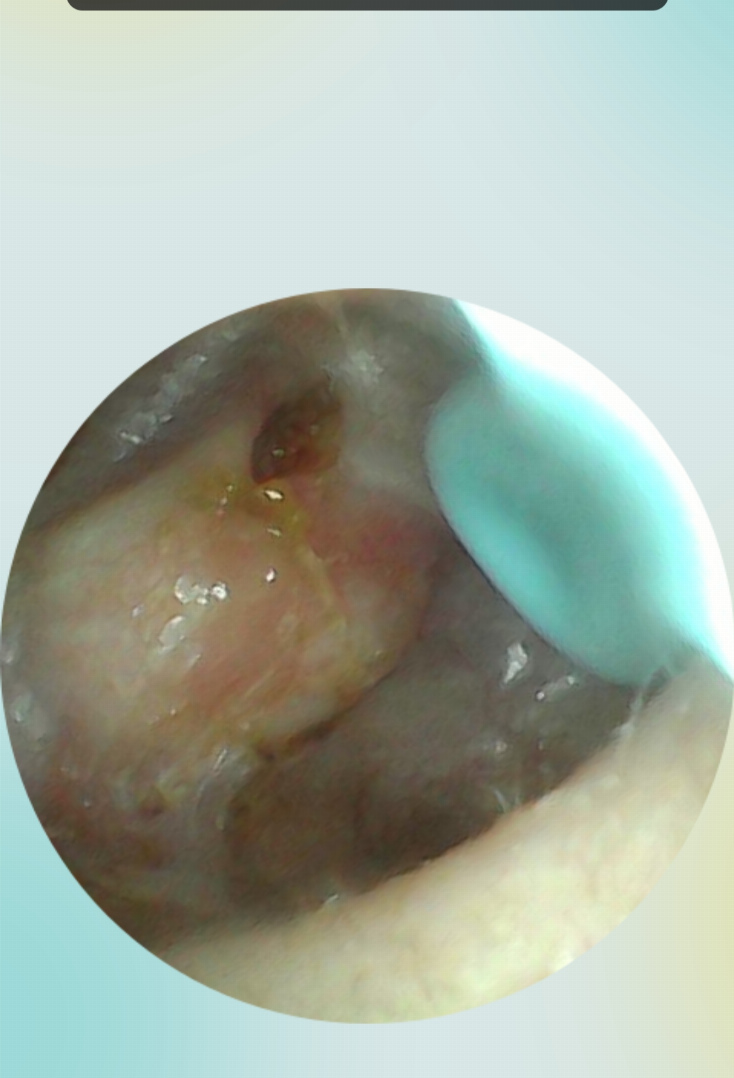

C’est en septembre 2022 que j’ai refait une énorme otite. Plus forte que toutes celles que j’avais connues, elle m’a conduit trois fois aux urgences tant la douleur était insupportable. Après ces multiples passages au CHU, j’ai fini par être examiné par l’ORL en chef du service, également chirurgien, et il a suspecté un cholestéatome. Un scanner a été réalisé la semaine suivante, et le diagnostic est tombé : c’était bel et bien un cholestéatome que je traînais depuis un moment et qui s’infectait, provoquant ces otites atroces.

L’opération a eu lieu, et elle s’est bien passée. J’ai perdu l’enclume et le marteau, car ils étaient trop rongés par la maladie, et une ossiculoplastie a été réalisée avec des cartilages prélevés directement sur mon oreille. Je n’ai eu aucun problème de douleur post-opératoire. Mon audition est revenue petit à petit, sur plusieurs mois, et s’est stabilisée au bout de neuf mois. J’ai perdu les fréquences au-dessus de 8 kHz, ainsi qu’un niveau sonore de -20 dB par rapport à l’oreille gauche. Cependant, le cerveau sait naturellement équilibrer l’audition. J’ai pu continuer à travailler malgré ma déficience, en réorganisant ma manière de travailler et en trouvant des outils de contrôle.

Début 2025, l’ORL m’a fait passer un nouveau scanner. Malheureusement, la maladie a récidivé. Je suis donc repassé sur la table le 30 avril. Le chirurgien en a profité pour affiner le travail sur l’ossiculoplastie et m’a annoncé qu’il y avait une probabilité que mon audition soit de meilleure qualité qu’après la première opération. Je suis actuellement en phase de récupération, et j’ai déjà pas mal retrouvé d’audition au bout d’un mois, contrairement à la première fois où cela avait semblé beaucoup plus long.